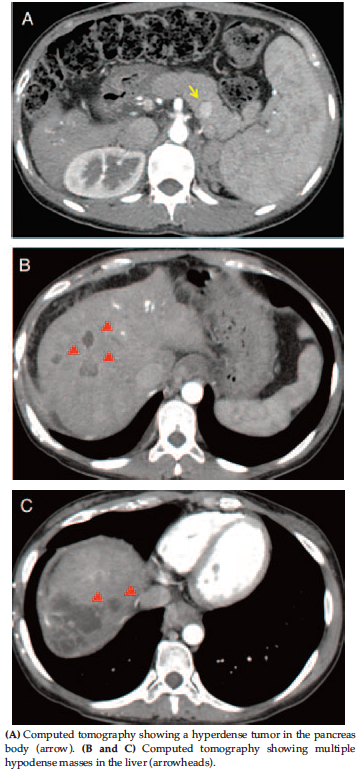

Magnetic resonance imaging showed cystic lesions suggesting biloma; however, metastasis could not be ruled out (Figure 2). She underwent endoscopic variceal ligation for bleeding prophylaxis caused by esophageal varices 3.1 years following SMANCS-TAE. The laboratory evaluation indicated liver failure with an increased total bilirubin level of 4.1 mg/dL, direct bilirubin level of 2.9 mg/dL, and platelet count of 63 000/μL. Liver transplant was indicated for hepatic failure, and the patient was referred to the department of transplantation at the Kumamoto University Hospital.

Figure 2. Abdominal Magnetic Resonance Imaging Findings (a)